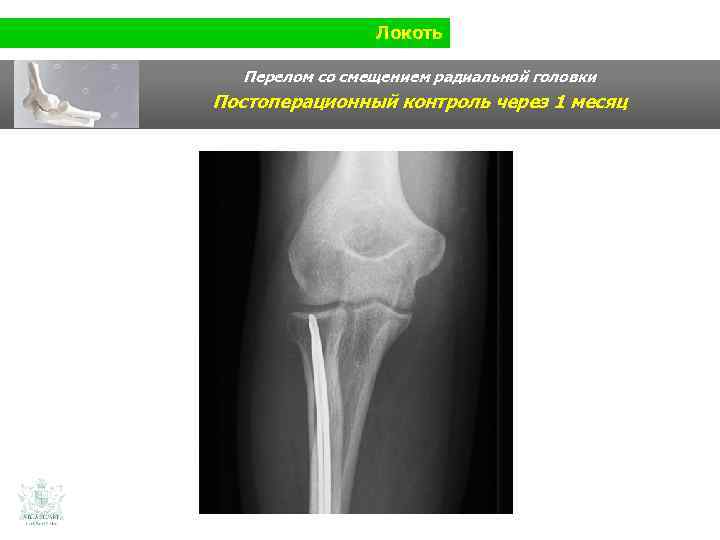

Локоть Перелом со смещением радиальной головки Постоперационный контроль через 1 месяц